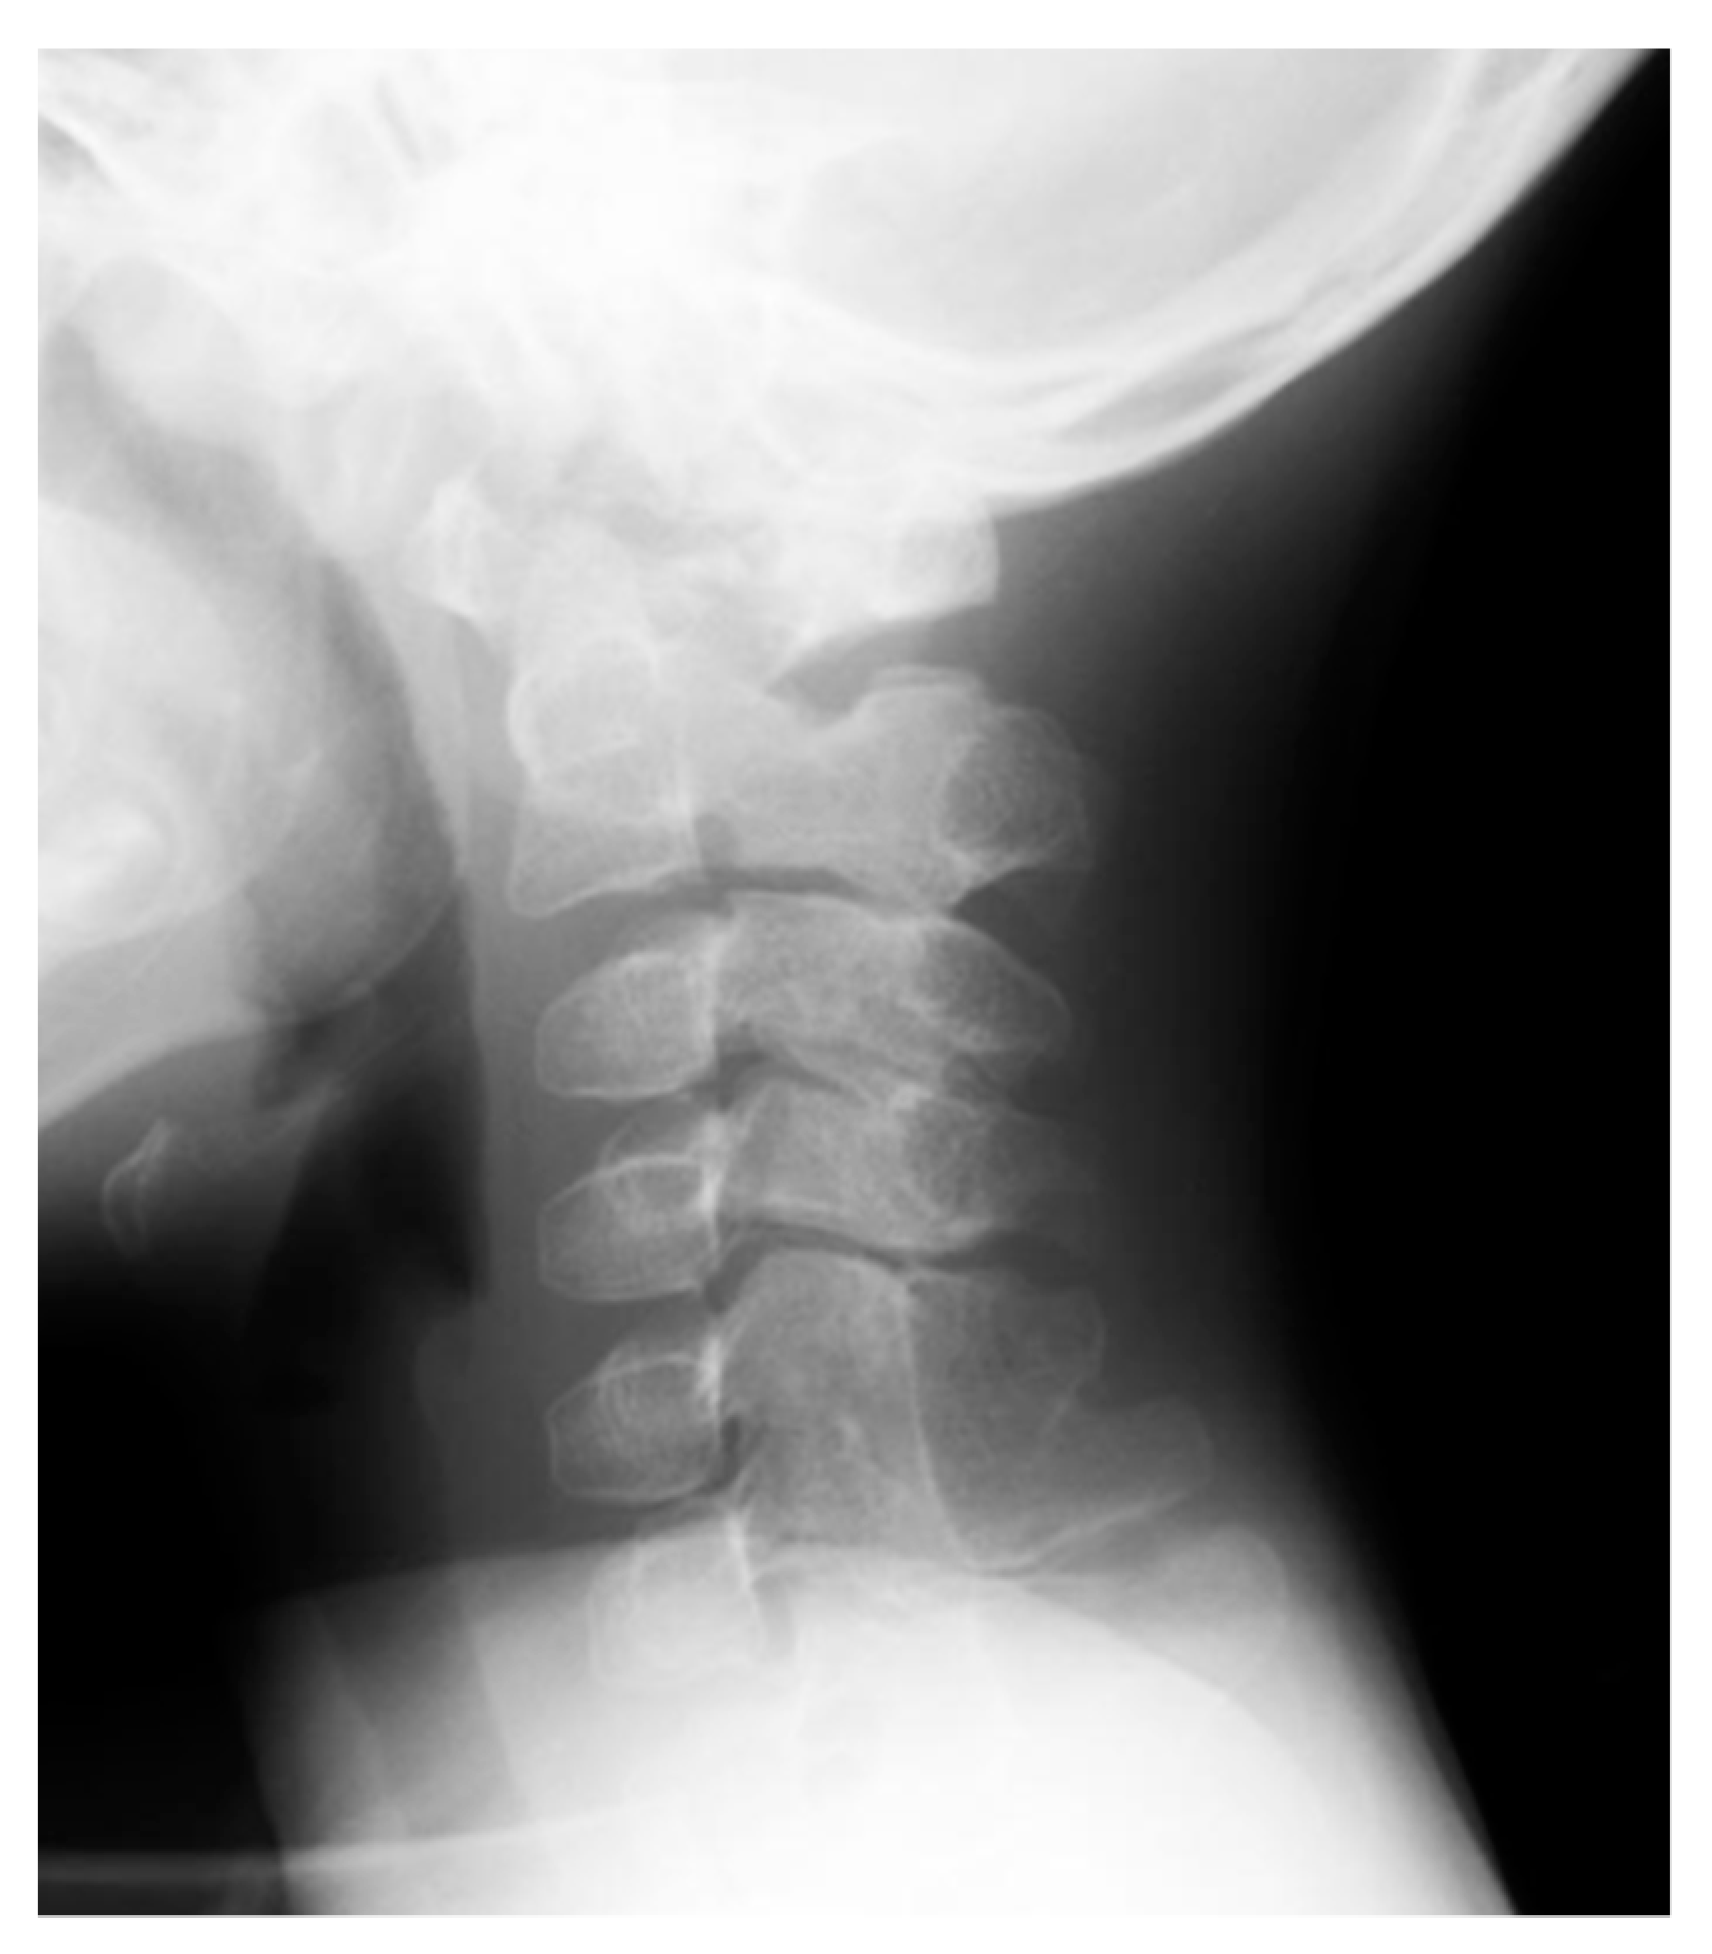

- Mishima, K.; Kitoh, H.; Haag, N.; Nakashima, Y.; Kamizono, J.; Katagiri, T.; Susami, T.; Matsushita, M.; Ishiguro, N. Radiographic characteristics of the hand and cervical spine in fibrodysplasia ossificans progressive. Intractable Rare Dis. Res. 2014, 3, 46–51. [Google Scholar] [CrossRef]

- Schaffer, A.A.; Kaplan, F.S.; Tracy, M.R.; O’Brien, M.L.; Dormans, J.P.; Shore, E.M.; Harland, R.M.; Kusumi, K. Developmental anomalies of the cervical spine in patients with fibrodysplasia ossificans progressiva are distinctly different from those in patients with Klippel-Feil syndrome. Spine 2005, 30, 1379–1385. [Google Scholar] [CrossRef]